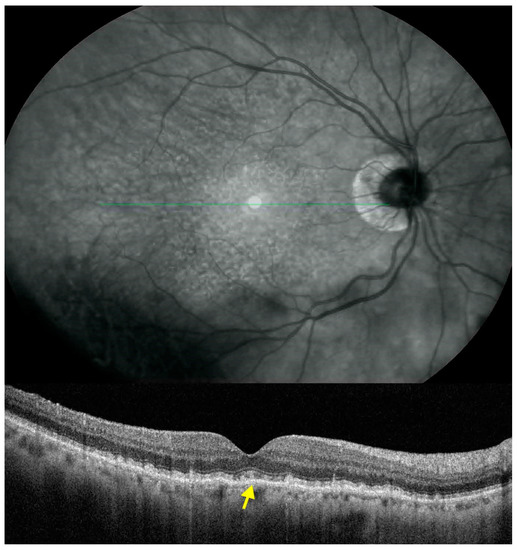

This was an observational cross-sectional study including 55 eyes of 55 subjects (18 eyes with SDD, 19 eyes with CD, and 18 eyes of healthy age-matched subjects) carried out at the Retina Centre of the Ophthalmology Unit of the University of Rome Sapienza, St. Andrea Hospital. The study had Institutional Review Board Approval from the University of Rome, Sapienza. All the procedures were performed in agreement with the principles of the declaration of Helsinki. Informed consent was obtained from the subjects after explanation of the nature of the study. Inclusion criteria were diagnosis of early/intermediate AMD in patients with age above 50 years and near infrared reflectance (NIR) and spectral domain optical coherence tomography (SDOCT) evidence of CD (defined as the CD group) or SDD (defined as the SDD group). Healthy age-matched subjects were included as the control group and were patients who underwent routine ophthalmological examination in our general ophthalmology clinic. Exclusion criteria were spherical equivalent above 4 Diopters; glaucoma or intraocular pressure above 18 mmHg or altered disk aspect such as notching, hemorrhage, thinning of the neuroretinal rim, cup to-disk ratio difference of more than 0.2 between fellow eyes and optic atrophy; diabetic retinopathy; hypertensive retinopathy; SDOCT evidence of epiretinal membranes; presence of neurological disease; and fundus autofluorescence evidence of the presence of retinal pigment epithelium (RPE) atrophy or vitelliform deposits. Each patient underwent comprehensive ophthalmoscopic examination including assessment of best corrected visual acuity (BCVA) and refractive error, slit lamp evaluation of the anterior segment, tonometry, and fundus examination. Photographic documentation of the posterior pole was performed using the photographic setting of the compass perimeter (Centervue). The evidence of SDD or CD was evaluated by two operators through the simultaneous evaluation of NIR images (Heidelberg HRT II) compared with raster images on SDOCT (Rtvue XR Avanti, Optovue, Inc, Fremont, CA, USA) according to the classification system proposed by Zweifel et al. and Spaide et al. [2,23]. Patients in the SDD group had to have evidence of at least 5 subretinal drusenoid deposits in the diameter of a papillary disc area. The presence of any CD equal to or larger than 63 μm was a reason for exclusion. Patients in the CD group had to have at least one drusen larger than 125 μm or 5 drusen between 63 and 125 μm. In order to better characterize the eyes under investigation, a quantification of the subfoveal lesions present in the two groups was made through a qualitative analysis of vertical and horizontal SDOCT scans centered on the fovea. In the SDD group 8 eyes out of 18 had subfoveal lesions (44%), while in the CD group 13 eyes out of 19 had subfoveal lesions (68%) (Figure 1). SDOCT evaluation in all patients and subjects was carried out with the following scan protocols: raster with 17 parallel-lines of standard length and width; grid with 5 vertical and 5 horizontal lines centered on the fovea; and retina map with thickness output organized in 9 Early Treatment Diabetic Retinopathy Study (ETDRS) zones, formed by circles of 1 mm, 3 mm, and 5 mm diameter centered on the fovea as defined by Gass [24]. Automated segmentation of the inner retina was carried out using Optovue software 2017.1.0.151 from the inner limiting membrane to the outer border of the IPL. Thickness values were recorded in the 9 central zones where the 3mm and 5mm diameter areas were further divided into superior, nasal, temporal, and inferior sectors [24]. Scans with quality inferior to 5/10 were rejected and re-acquired. Two expert investigators (MDP, ES) evaluated automated segmentation to check for any misalignment and in case of doubt, a senior investigator (SA) was consulted. No cases of misalignment were observed. In bilateral AMD, the choice of the eye included for analysis in the SDD and CD group was based on exclusion criteria; in the SDD and CD groups 12 and 9 fellow eyes had exclusion criteria, respectively. When both eyes in the SDD, CD, and healthy control groups could potentially be included, according to the inclusion/exclusion criteria, we used a random number generator where odd numbers were for right eyes and even numbers for left eyes. Data were expressed as mean ± standard deviation or median and interquartile range for continuous variables, and the number of cases (and percentages) for categorical variables. All variables were tested for normality using the non-parametric Kolmogorov-Smirnov test. Continuous variables were compared by the analysis of covariance (ANCOVA), adjusted for age, and a post-hoc Tukey HSD correction analysis was performed for multiple comparison analysis. Differences between means of SDD and CD group were tested using t-test with Bonferroni correction when required. Categorical variables were evaluated using the χ-square test or Fisher exact test when appropriate. A p value ≤ 0.05 was considered statistically significant.

Figure 1.

Spectral domain optical coherence tomography (SDOCT) scan of an eye with subfoveal subretinal drusenoid deposits (SDD). The SDOCT cross-sectional scan shows hyperreflective material between the retinal pigment epithelium and the ellipsoid zone with focal changes of the latter. SDD located under the fovea is shown with the arrow.